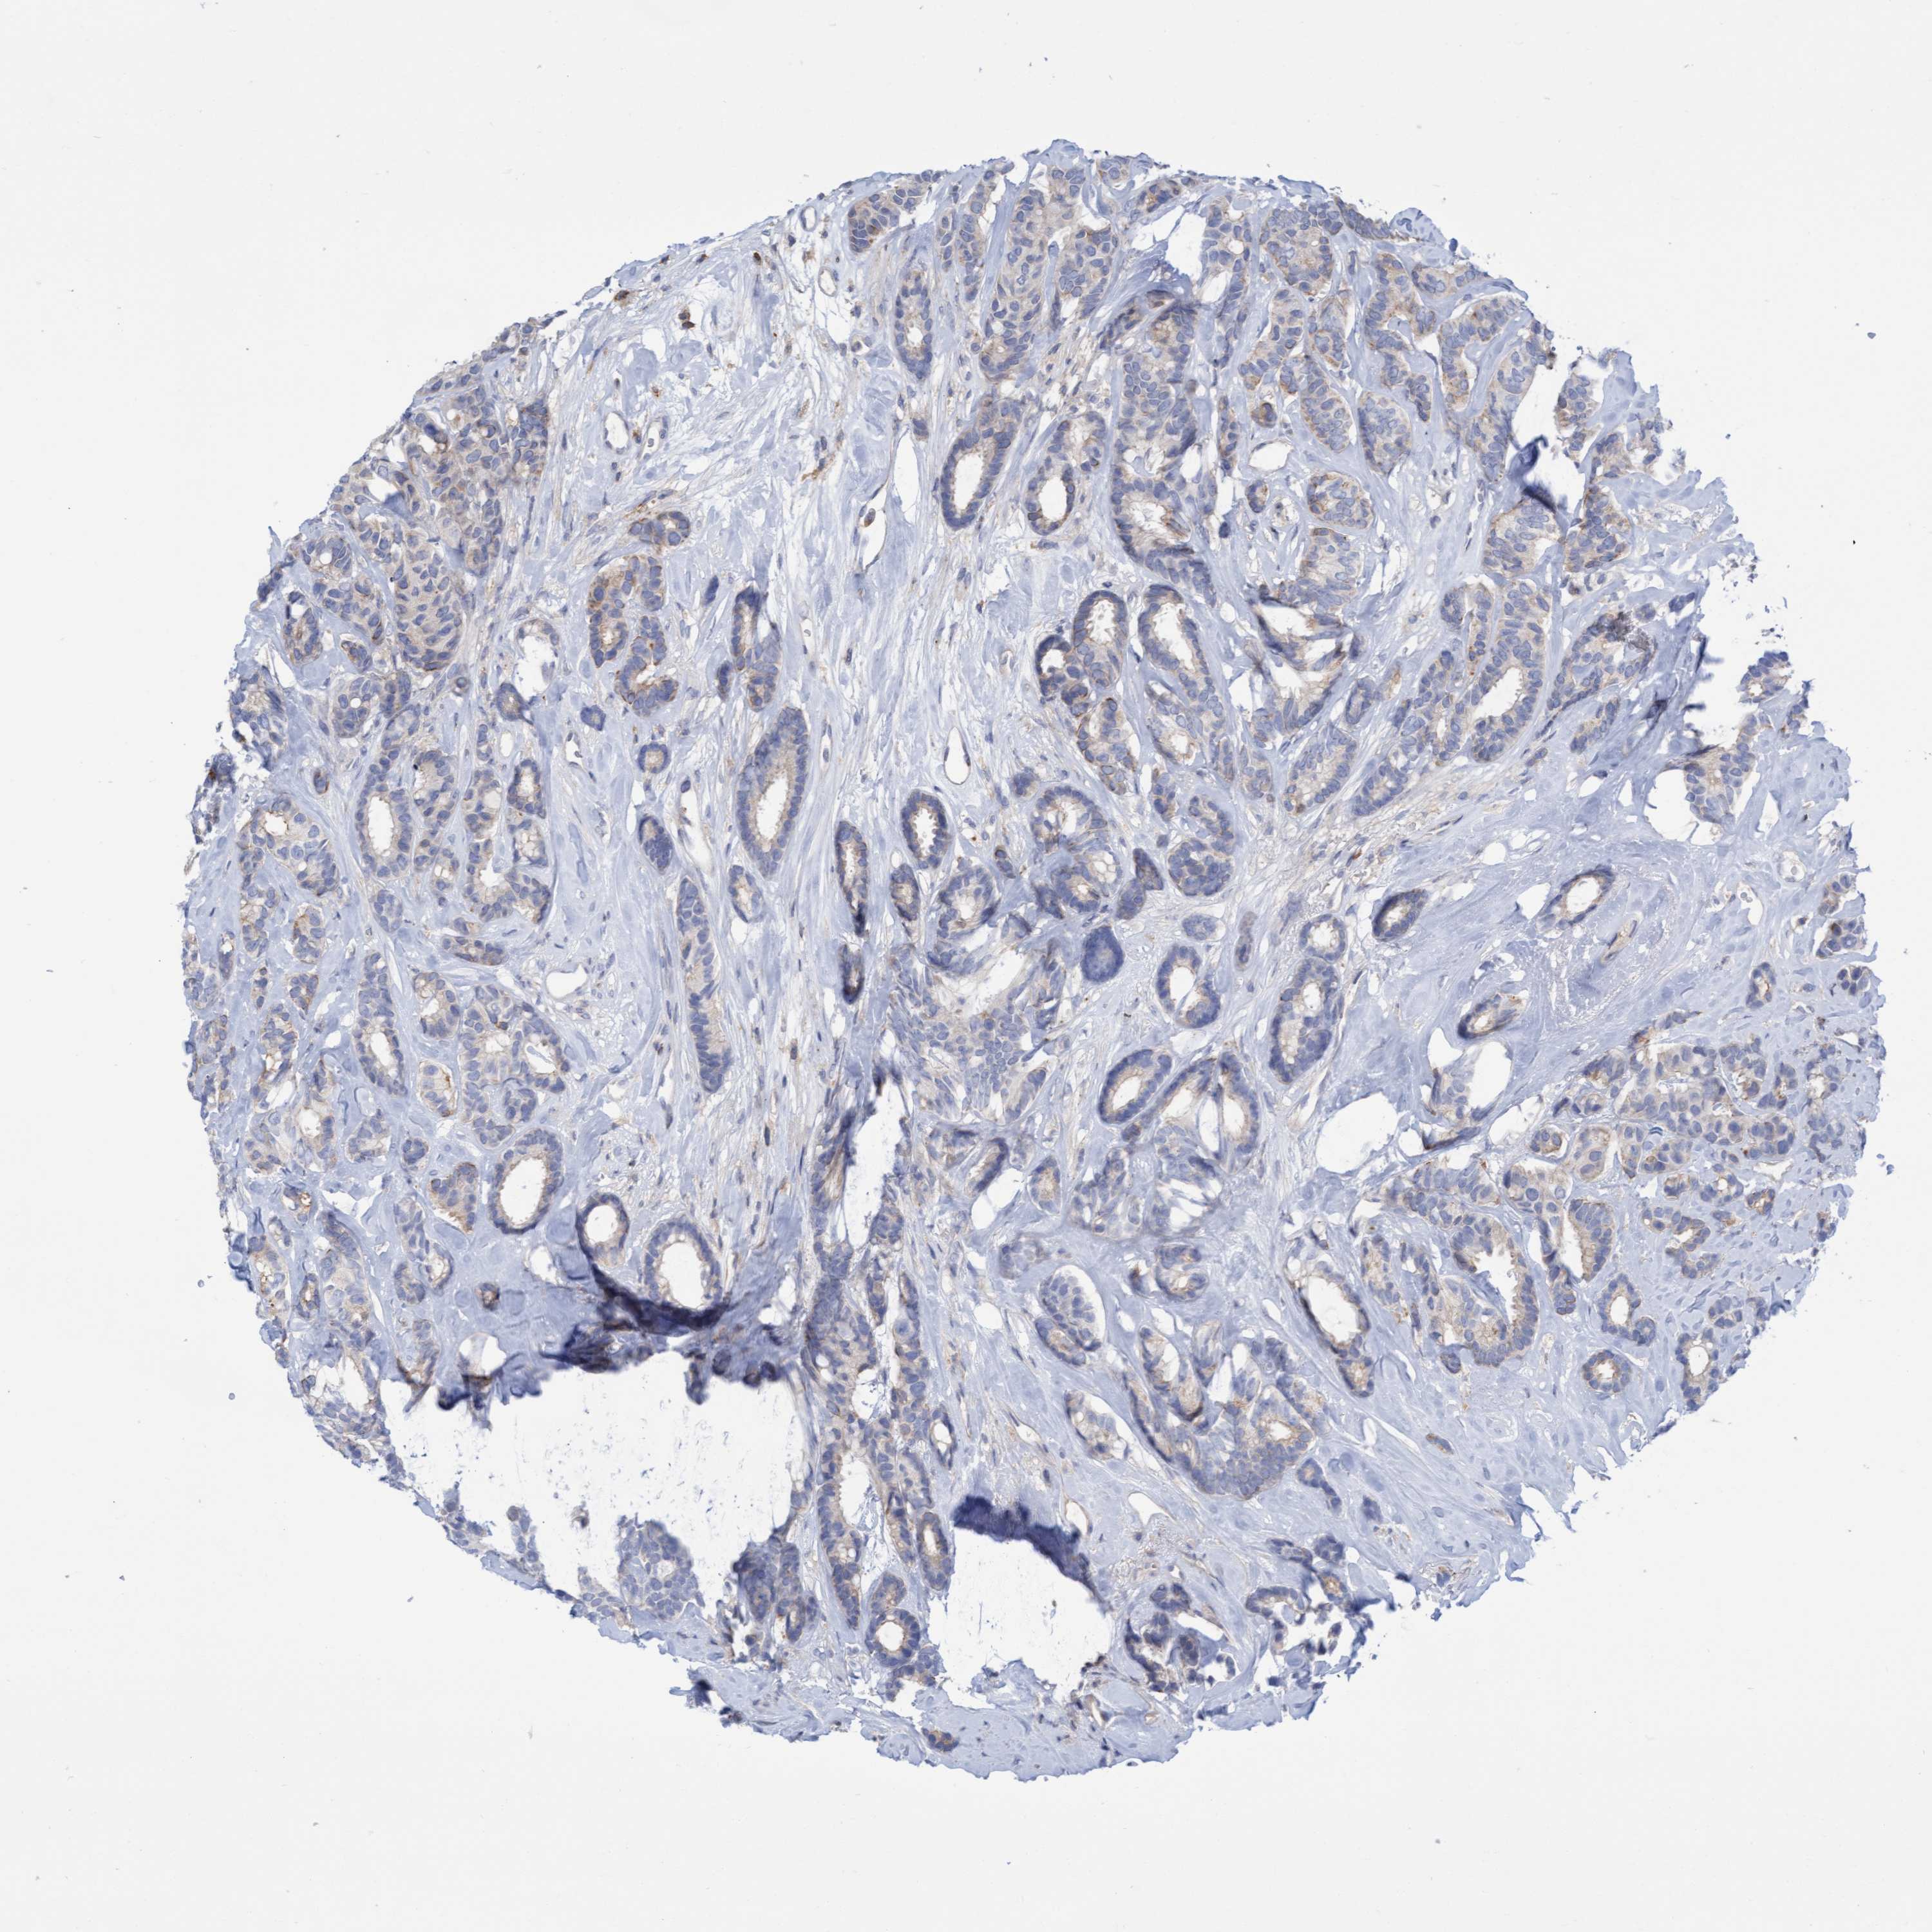

CANCER BREAST CANCER Show tissue menu

BRCA TCGA BRCA VALIDATION PROTEIN EXPRESSION

Breast cancer

Human cancer